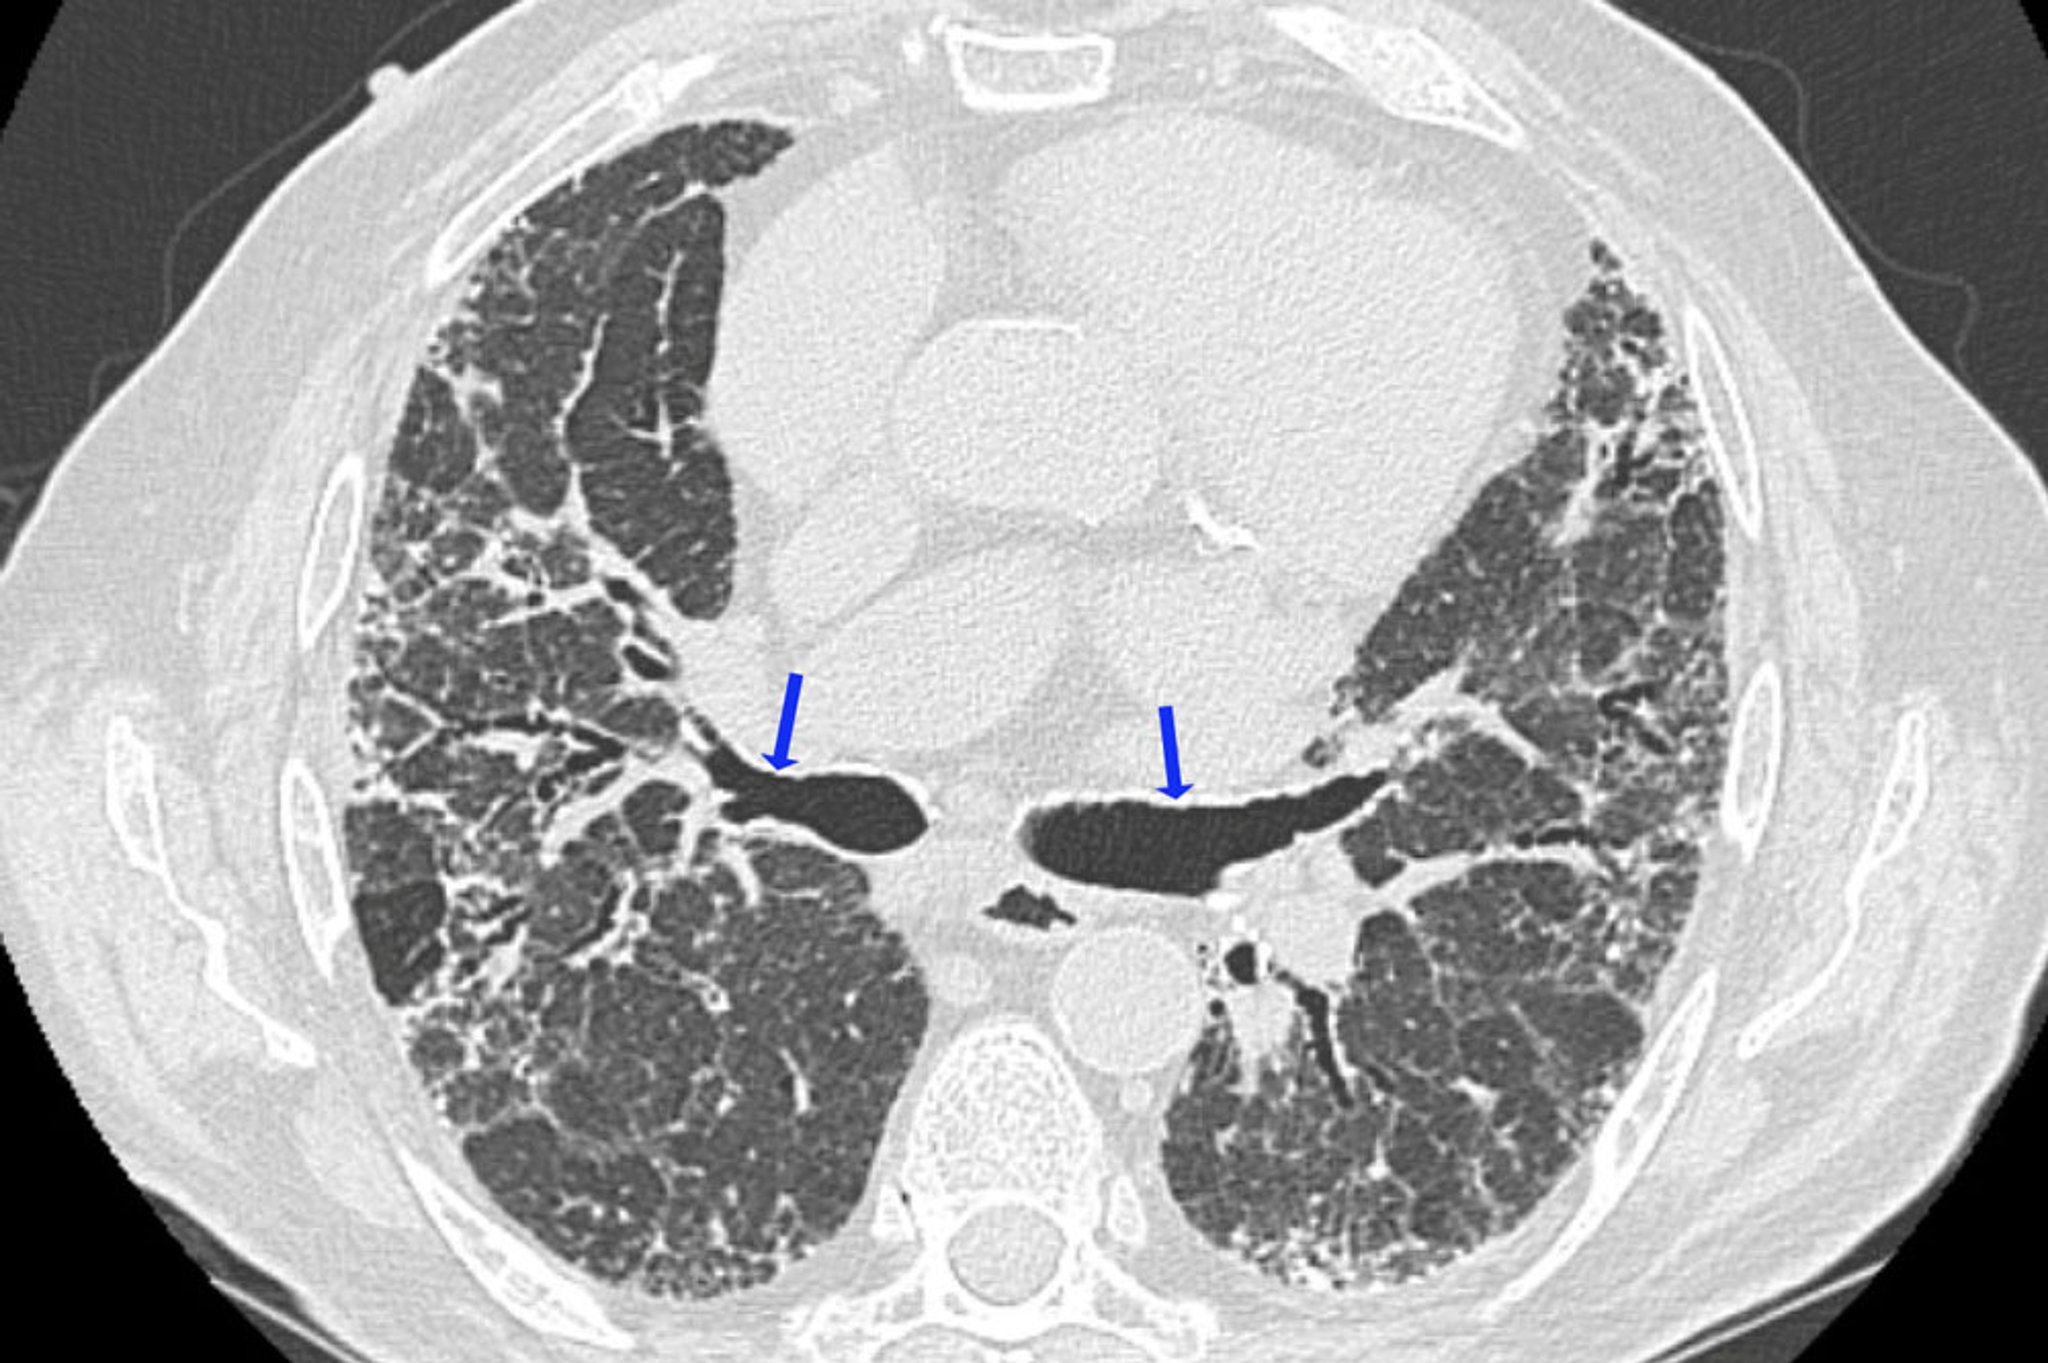

High-resolution CT is the preferred imaging modality for evaluating parenchymal changes in hypersensitivity pneumonitis, and is more likely to show abnormalities than standard CT or radiographs (2).

In acute and subacute hypersensitivity pneumonitis, the most typical HRCT findings are centrilobular micronodules, typically measuring less than 3 mm in diameter, usually located near the central airways of those lobules. Occasionally, ground-glass opacification (attenuation) is the predominant or sometimes the only finding. It is usually diffuse but sometimes spares the periphery of the secondary lobule. Focal areas of hyperlucency, similar to those present in bronchiolitis obliterans, may be a prominent feature in some patients (eg, mosaic attenuation with air trapping on expiratory HRCT).

In chronic hypersensitivity pneumonitis, there are findings of lung fibrosis, which include lobar volume loss, linear or reticular opacities, honeycombing, and traction bronchiectasis. Centrilobular micronodules, ground-glass opacification, and areas of hyperlucency may occur but are less prominent. Some patients with chronic hypersensitivity pneumonitis who do not smoke have findings of upper lobe emphysema. Mediastinal lymphadenopathy is uncommon, thereby distinguishing hypersensitivity pneumonitis from sarcoidosis.